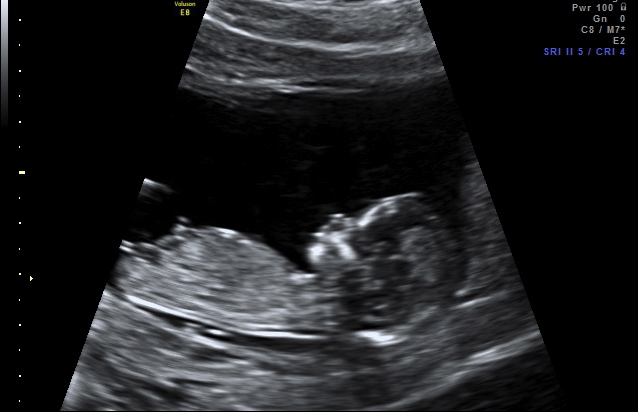

Hi everyone, could you take a guess from this nub shot? It was taken at 12 w 4 d officially, but the baby measured in at 13 w 1 d.

Thank you! :flowerz:Attachment 908Attachment 909